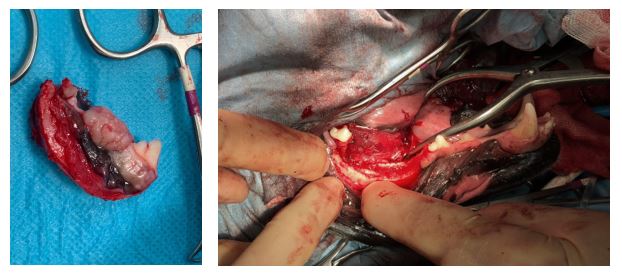

2. Treating a benign but invasive oral tumour

These are pictures of a rim resection of a mandible for a acanthomatous ameloblastoma (a benign but invasive oral tumour) in a dog. This type of resection is conservative in its approach, biomechanically secure in its design and maintains normal occlusion. It can be a very good option for treating less aggressive or invasive forms of tumours affecting the mandible in medium and large breed dogs.